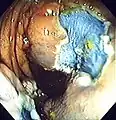

Colonoscopy (/ˌkɒləˈnɒskəpi/) or coloscopy (/kəˈlɒskəpi/)[1] is the endoscopic examination of the large bowel and the distal part of the small bowel with a CCD camera or a fiber optic camera on a flexible tube passed through the anus. It can provide a visual diagnosis (e.g., ulceration, polyps) and grants the opportunity for biopsy or removal of suspected colorectal cancer lesions.

![]() Colonoscopy being performed | |